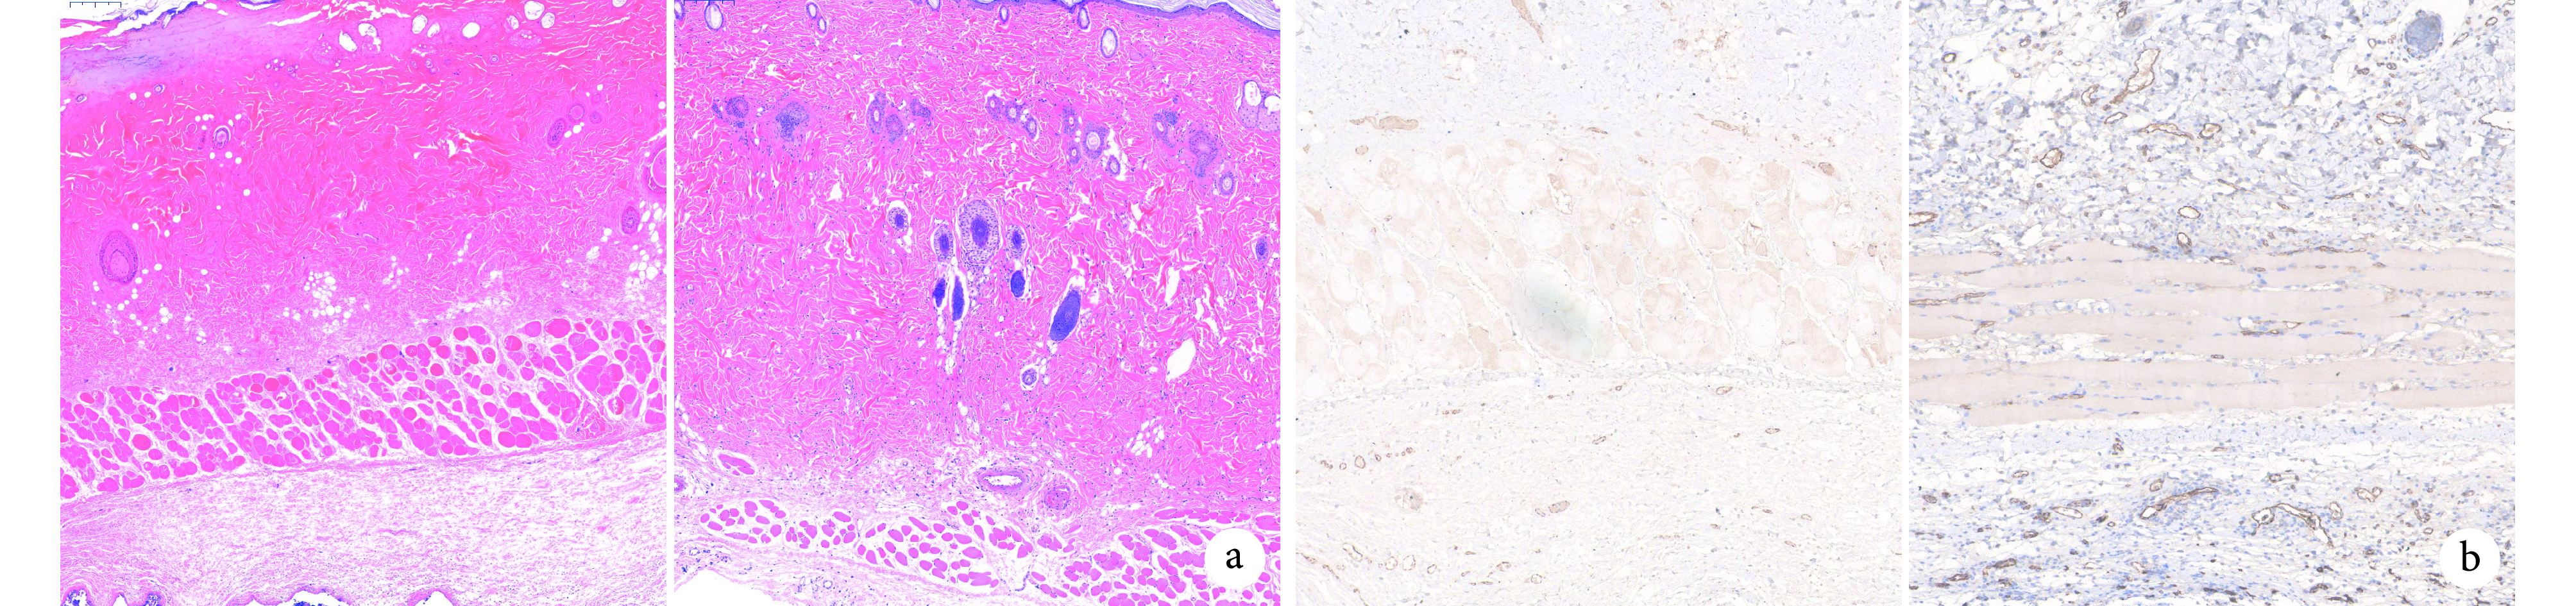

術后第 7 天兩組皮瓣遠端區域組織形態相似,皮膚結構表現出不同程度壞死現象,但 ADSC-Exos 組略好于 PBS 組;中間區域 ADSC-Exos 組皮膚附屬器官較 PBS 組更完整;近端區域兩組均可見少量炎性細胞浸潤,但 ADSC-Exos 組與 PBS 組相比,組織水腫程度輕、血管擴張更多。見圖5a。

左側為 PBS 組,右側為 ADSC-Exos 組 a. HE 染色(×200);b. CD31 免疫組織化學染色(×100)

Figure5. Histological and CD31 immunohistochemical staining observations of two groups on the 7th dayLeft for the PBS group and right for the ADSC-Exos group a. HE staining (×200); b. CD31 immunohistochemical staining (×100)

2.3.3 免疫組織化學染色觀察

鏡下見 ADSC-Exos 組皮瓣中間部位組織中出現大量成熟新生血管,伴有新生血管側支形成,新生血管基本擴張;PBS 組新生血管形成較少或處于內皮細胞萌發階段,血管擴張不明顯。ADSC-Exos 組 MVD 為(103.3±27.0)個/視野,顯著多于 PBS 組(45.3±16.2)個/視野,差異有統計學意義(t=3.190,P=0.011)。見圖5b。